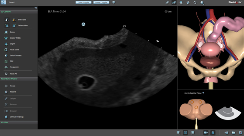

BASIC GYNAE TVS MODULE:

New Dedicated Separate Platform!

Physicians and Sonographers have the opportunity to practice varied common scenarios of routine or emergency Transvaginal Sonography.

True-to-life anatomies and pathologies include normal anatomical variations, early IUP, ectopic pregnancy, fibroids, ovarian malignancies, hydrosalpynx and more.

Step-by-step procedural tasks offer self learning of the standard positions to be demonstrated in TVS protocols.